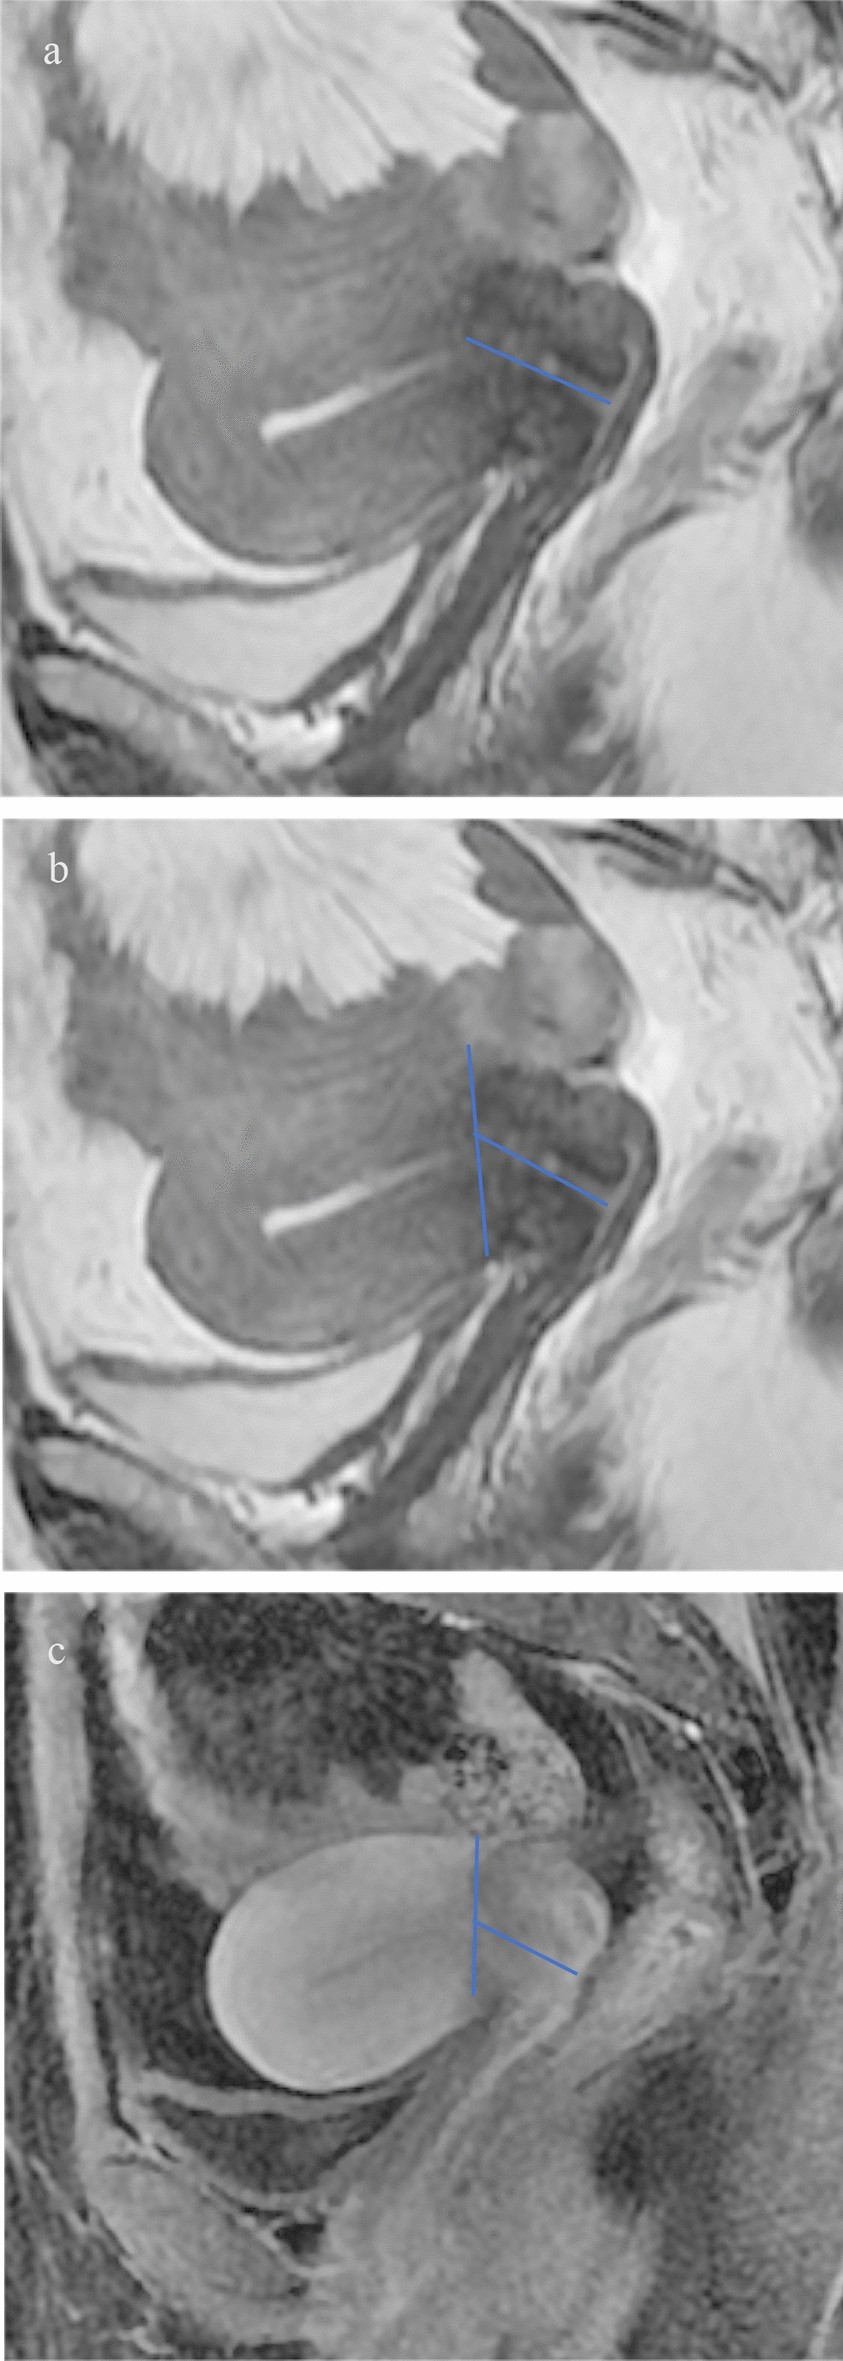

Figure 3

Sagittal T2WI, measure the cervical length from the start of the low signal of the cervical stroma (a). Sagittal T2WI, measures the cervix length starting from the cross-section where the physiological curvature of the uterus is formed (b). Sagittal dynamic enhancement scanning image, measure the cervix length beginning from the uterine and cervical enhancement junction (c).